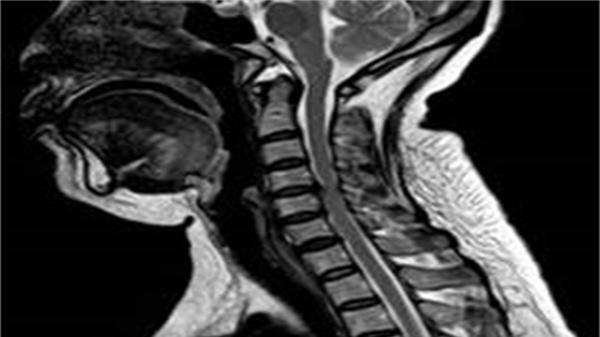

创新降期方案重获手术机会

付大伯入院后 , 经过全方位检查 , 最终被确诊为肝内胆管细胞癌(肝内多发转移、淋巴结转移) , AJCC分期(由美国癌症联合委员会与国际抗癌联合会共同制定 , 目前最为流行的分期方式)为ⅢB期 , 即晚期 , 不推荐手术治疗 。 随后 , 王伟林院长联合放射科、超声医学科、肿瘤内科、病理科等多学科开展全面评估与讨论 , 结合基因检测结果及付大伯身体情况 , 最终选择“GPLET方案”(化疗联合免疫靶向治疗)作为付大伯术前转化治疗的方案 , 经过4个周期治疗 , 核磁共振影像显示病灶及腹膜后淋巴结均明显缩小 。

降期成功!经过评估 , 此时付大伯的状况已符合手术标准 , 王伟林院长当机立断 , 主刀为付大伯实施了“右半肝切除术+肝门部及后腹膜淋巴结清扫术” , 历时3小时 , 手术圆满成功 。